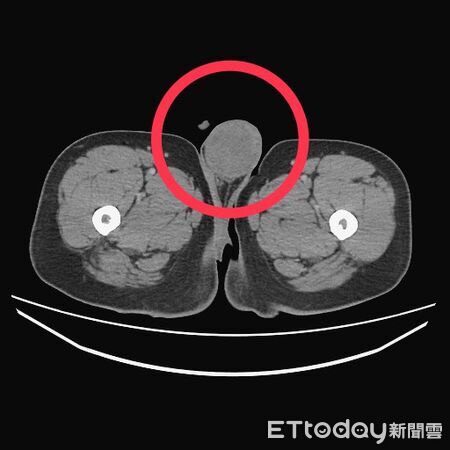

▲台中七期百貨男到院檢查,才發現左側睪丸有一顆5.5公分大腫瘤,且已全身轉移。(圖/醫師江佳駿提供)

衛生福利部台中醫院血液腫瘤科主治醫師江佳駿表示,患者入院後經X光及電腦斷層掃描檢查,結果發現,其體內已遭腫瘤「塞爆」,範圍涵蓋肺臟、肝臟及後腹腔。進一步追查發現,病源來自左側睪丸一顆5.5公分的惡性腫瘤,且後腹腔也有一顆高達12公分的巨大腫瘤,確診為睪丸癌末期且已廣泛轉移。